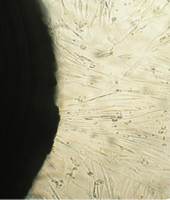

Вид монослоя и структура клеток не отличались от обычных в течение всех четырех суток наблюдения (рис. 32).

Это свидетельствует об умеренной стимуляции пролиферации фибробластов в культуре под влиянием недеминерализованной спонгиозы (таб. 9.).